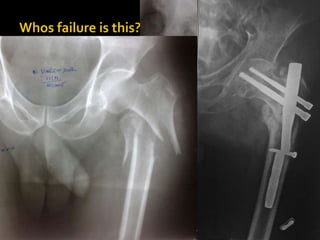

If neither have been followed, it is not right to

blame the nail or the device or to look for a new

design

Complication entirely relatedto Surgeon/ technical error